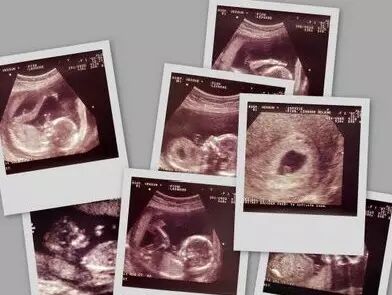

在整个孕期,定期产检中会要求三次B超检查,分别为孕18-30周、孕28-30周以及孕37-40周。第一次的B超目的是了解胎儿属于单胎还是多胎。第二次B超则为排畸检查。第三次B超为分娩前的评估。如果按照正常程序与数量进行B超,则不会对胎儿产生不良影响。不过,如果B超进行过早或者每次时间过长,则很有可能会危及到胎儿的健康状况。因此,在做B超时,要严格按照医生的指导,切莫随意做检查。